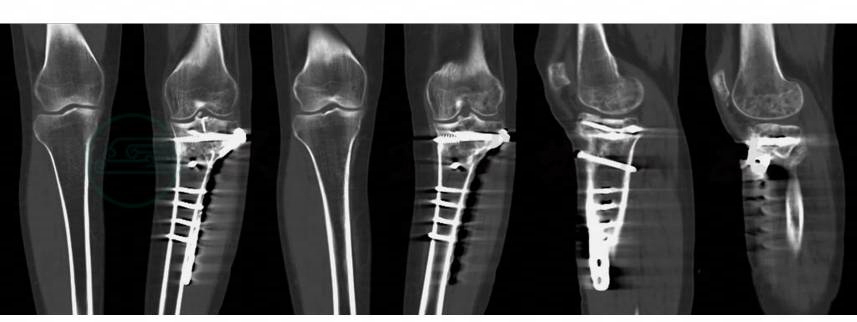

图3 术前CT

专科查体:患者跛行。左膝前侧及外侧可见创伤及手术切口瘢痕,左膝明显内翻畸形(图1)。左胫腓骨近端压痛,叩击痛。骨擦音及反常活动未及。左膝关节伸屈活动范围:0°~120°。大转子至内踝尖:右65cm;左63cm。浮髌试验、外翻应力试验、抽屉试验、Lachman试验阴性,内翻应力试验阳性。左下肢肢端皮肤温暖,色泽正常,弹性好,毛细血管再充盈时间正常,足背动脉、胫后动脉搏动正常,肢体肌肉牵拉痛阴性,皮肤痛触觉正常,足趾主动活动正常。X线片可见胫骨平台骨折术后,膝关节内翻畸形(图2)。CT所示膝关节关节面良好,膝内翻主要存在于关节外部分(图3) 。